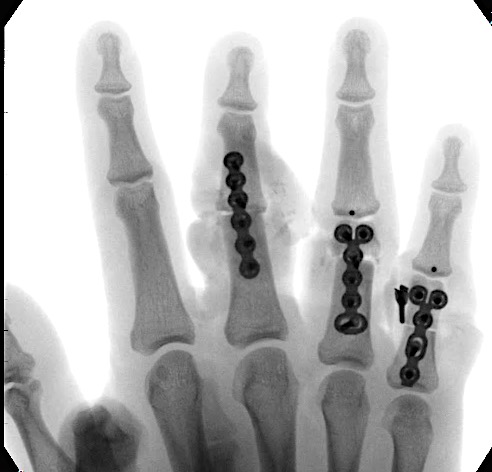

A 20-year-old male suffered a complex multi-digit injury of the right hand requiring revascularization and stabilization of both proximal phalanx and PIP joint fractures (Figs 5 - 8). Multiple plates, including the rotation correction plate from the 1.5 module of the VA Locking Hand System were used for fixation. The Variable Angle Locking system is ideal when only two screws, either proximal or distal, are able to be inserted due to space limitation.

One major advantage of variable angle technology in very distal phalangeal fractures is the ability to be extremely flexible with a wide range of fixation options. Freedom of implant placement assists early mobilization, vital in these complex fractures with associated soft-tissue trauma.